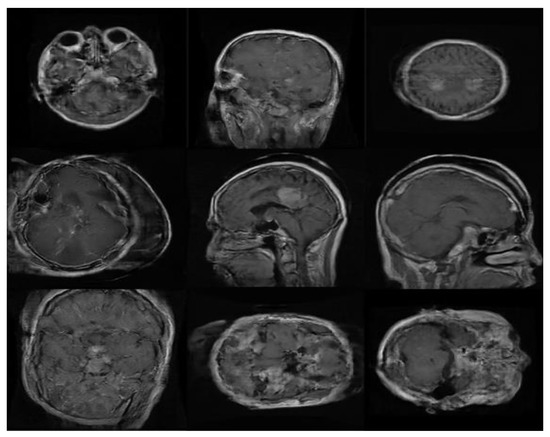

2.1. Data set for the Study